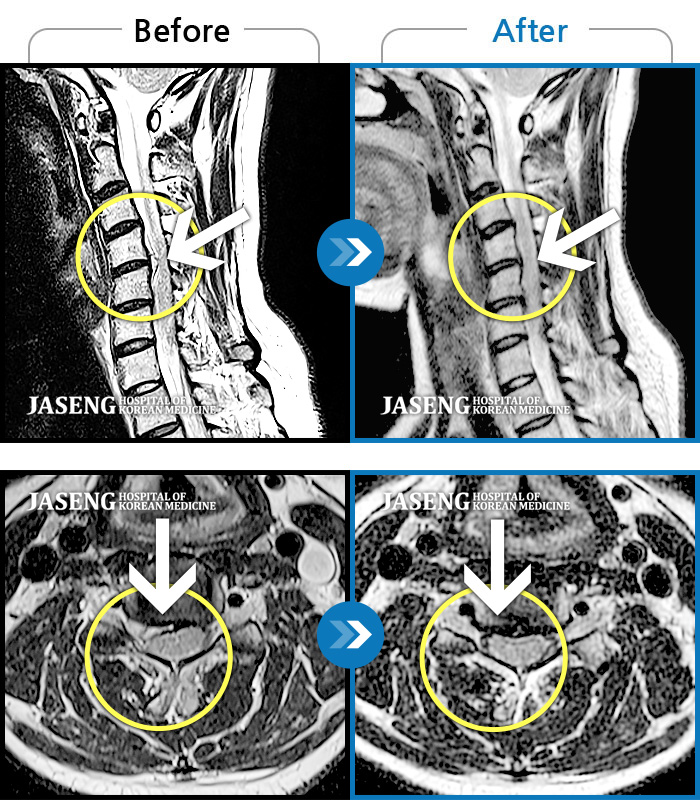

Before

After

환자에게 사전 동의를 받아 동일 조건에서 촬영되었습니다.

개인에 따라 치료 후 부작용이 발생할 수 있으니 의료진과 상담 후 치료를 진행하시기 바랍니다.

갑작스런 통증으로 보행이 불가하고 수면을 못하는 상태로 내원함

허리 통증이 심해서 앉아 있을 수가 없어요.